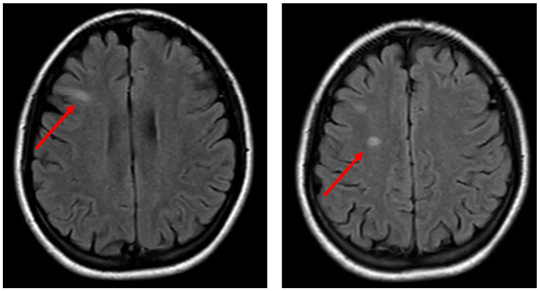

The thymic gland and pancreas were also prominent on the scans, suggestive of thymic hyperplasia and autoimmune pancreatitis, respectively, hence our rationale for evaluating her IgG-4 levels (Figure 2). During this time, the patient began displaying new vertical nystagmus. A magnetic resonance imaging (MRI) scan of the brain illustrated small areas of abnormal signaling in the right frontal lobe (Figure 3). The patient was transferred to the critical care unit for further management and was stabilized with intravenous fluids and antibiotics including azithromycin, 500 mg, daily and ceftriaxone, 1 mg, daily for 5 days.

Figure 3. A magnetic resonance imaging scan showed small areas of abnormal signaling in the right frontal lobe.

The cardiac findings in our patient—including the initial EKG changes suggestive of ischemia, elevated troponin and NT-pro-BNP levels, and global hypokinesis with reduced ejection fraction—and subsequent resolution of wall motion abnormalities are diagnostic for acute myocarditis and has been well-documented in children with MIS-C.17 Our patient’s multifocal neurological deficits of vertical nystagmus, diplopia, and MRI hyperintensities are suggestive of immune-mediated central nervous system inflammation like that seen in acute disseminated encephalomyelitis, which may have been ameliorated by early steroid use. Similar episodes of encephalopathy, cerebellar signs, and even cerebral infarct have been documented in MIS-C cases with negative cerebrospinal fluid findings.15,18,19 Our patient’s C-reactive protein level was elevated upon admission, but her erythrocyte sedimentation rate was within normal limits, which may have suggested a very early inflammatory process. Her complete resolution of symptoms in the setting of steroid administration also suggests a monophasic inflammatory syndrome, possibly post-infectious, vs autoimmune rheumatic syndromes that may relapse over time.